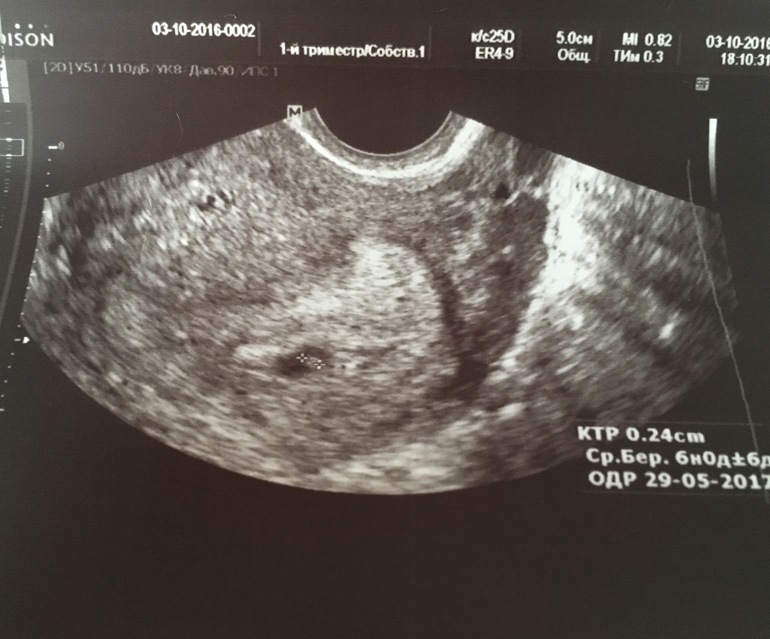

Наше первое фото))

Итак, по месячным срок 5 недель 4 дня. Размер плодного яйца 9,6 мм, а эмбриончика-2,4 мм. В заключении написали гипертонус миометрия по задней стенке. Несколько раз спросили, не болит ли живот, нет ли выделений, не было ли эндометриоза. Нет, ттт. Ничего такого. Надеюсь, тонус временный. Из-за того, что я немного опаздывала и нервничала.

Ну, и напоследок, наше фото)))